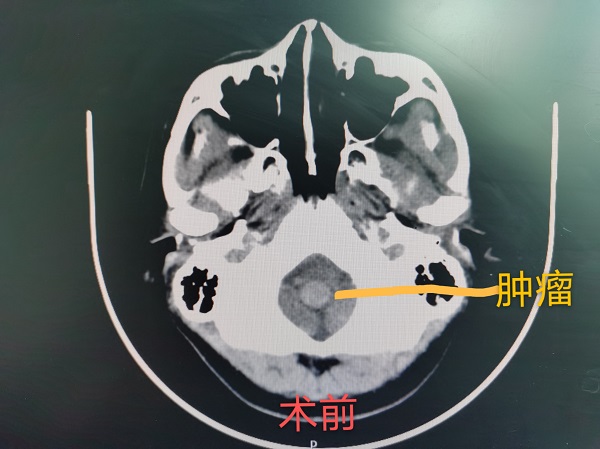

神經(jing)外科(ke)成(cheng)功完成(cheng)總醫(yī)院第30例腦幹腫瘤切除術(shù)

近日(ri),神經(jing)外科(ke)成(cheng)功完成(cheng)我(wo)院第30例腦幹腫瘤切除術(shù)。該患者爲(wei)一(yi)名(míng)37歲的(de)女性,因左側肢體(ti)活動(dòng)障礙入院治療,術(shù)中(zhong)見腫瘤位于(yu)延髓內(nei)部(bu),伴有(yǒu)出血,龐克軍主(zhu)任在(zai)顯微鏡下清(qing)除血腫,同時分(fēn)塊切除腫瘤,手術(shù)順利,術(shù)後(hou)患者肢體(ti)活動(dòng)恢複良好,按期出院。

自2017年(nian)總醫(yī)院成(cheng)功開展(zhan)第一(yi)例腦幹腫瘤手術(shù)以(yi)來,随着神經(jing)外科(ke)顱底顯微神經(jing)外科(ke)技(ji)術(shù)不斷(duan)成(cheng)熟,近幾年(nian)随着全國(guo)醫(yī)保聯(lian)網工(gong)作(zuò)的(de)推進(jin),外地來院就診的(de)腦幹腫瘤及(ji)複雜病例不斷(duan)增多(duo),腦幹腫瘤手術(shù)風險高(gao)、時間長(zhang),但昰(shi)在(zai)顯微神經(jing)外科(ke)技(ji)術(shù)成(cheng)熟的(de)前(qian)提下,随着神經(jing)內(nei)鏡咊(he)定向導(dao)航等(deng)新(xin)技(ji)術(shù)的(de)應用(yong),總醫(yī)院神經(jing)外科(ke)手術(shù)的(de)安(an)全性得到(dao)了(le)充分(fēn)保障。